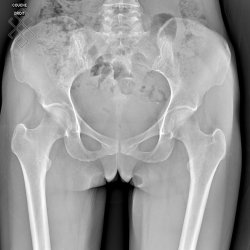

Radiographie du Bassin et Hanches

Pour une radiographie du bassin et hanche(s), aucune préparation n'est requise. Il est recommandé d'enlever tous les bijoux avant de se présenter.

Vous serez installés en position debout.

La durée de l'examen est d'environ 5 minutes.

Après la fin de la radiographie du bassin et hanche(s), vous pourrez continuer vos activités de la journée sans problème. S'il y a eu une injection, le manipulateur en radiologie retirera le cathéter et il vous sera recommandé de boire beaucoup d'eau afin d'éliminer au mieux le produit de contraste.

Avant de passer une radiographie du bassin et hanche(s), il est primordial de signaler si vous êtes ou pensez être enceinte. En effet, vous devrez passer l'examen sous certaines conditions.